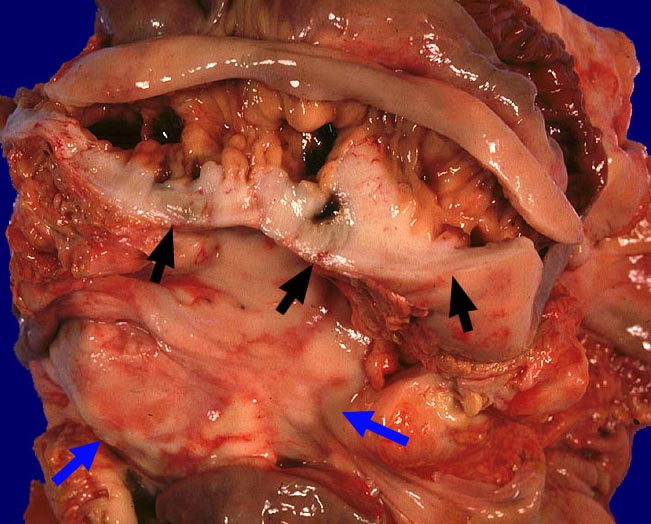

Diffuses grosszelliges B-Zell-Lymphom (WHO)

Mesenterium

Eröffnetes Jejunum mit anhaftendem Mesenterium. Das Mesenterium und die Jejunumwand sind diffus lymphominfiltriert.

Befall abdominaler Lymphknoten.

St.n. Chemotherapie.